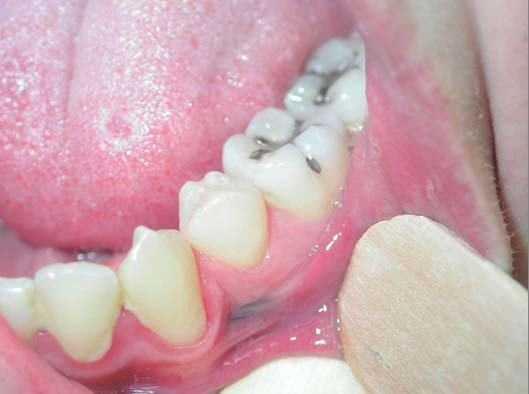

En la exploración cutánea se observa una lesión maculosa de color azul oscuro de 6 mm, homogénea en coloración y de bordes netos, localizada en la región gingival inferior izquierda (fig. 1). Esta mácula asentaba sobre el área gingival de la pieza dental anterior a los molares empastados (fig. 2). En la exploración con dermatoscopia (dermatoscopio Heine) se observa una pigmentación grisácea y azulada homogénea, sin patrón de red pigmentaria melánica.

Figura 1.

Figura 2.